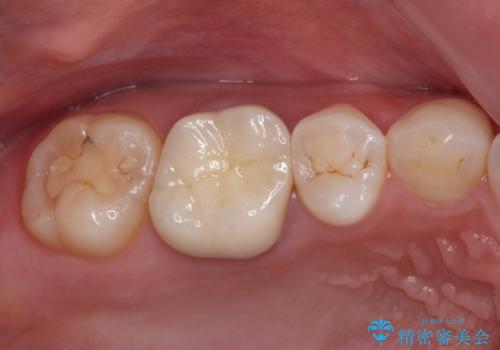

口腔内から、土台も含め銀歯がなくなったことでメタルフリーとなりました。